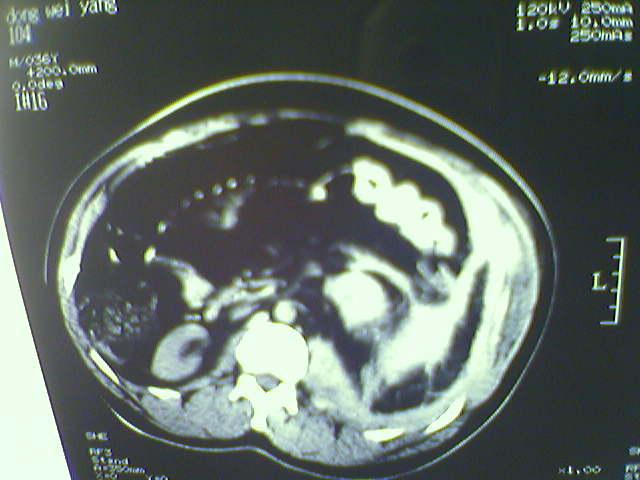

以下是引用lxq2000在2008-6-3 22:28:00的发言:[br]腹腔积液,腹壁软组织及左侧腰大肌肿胀建议mr检查。